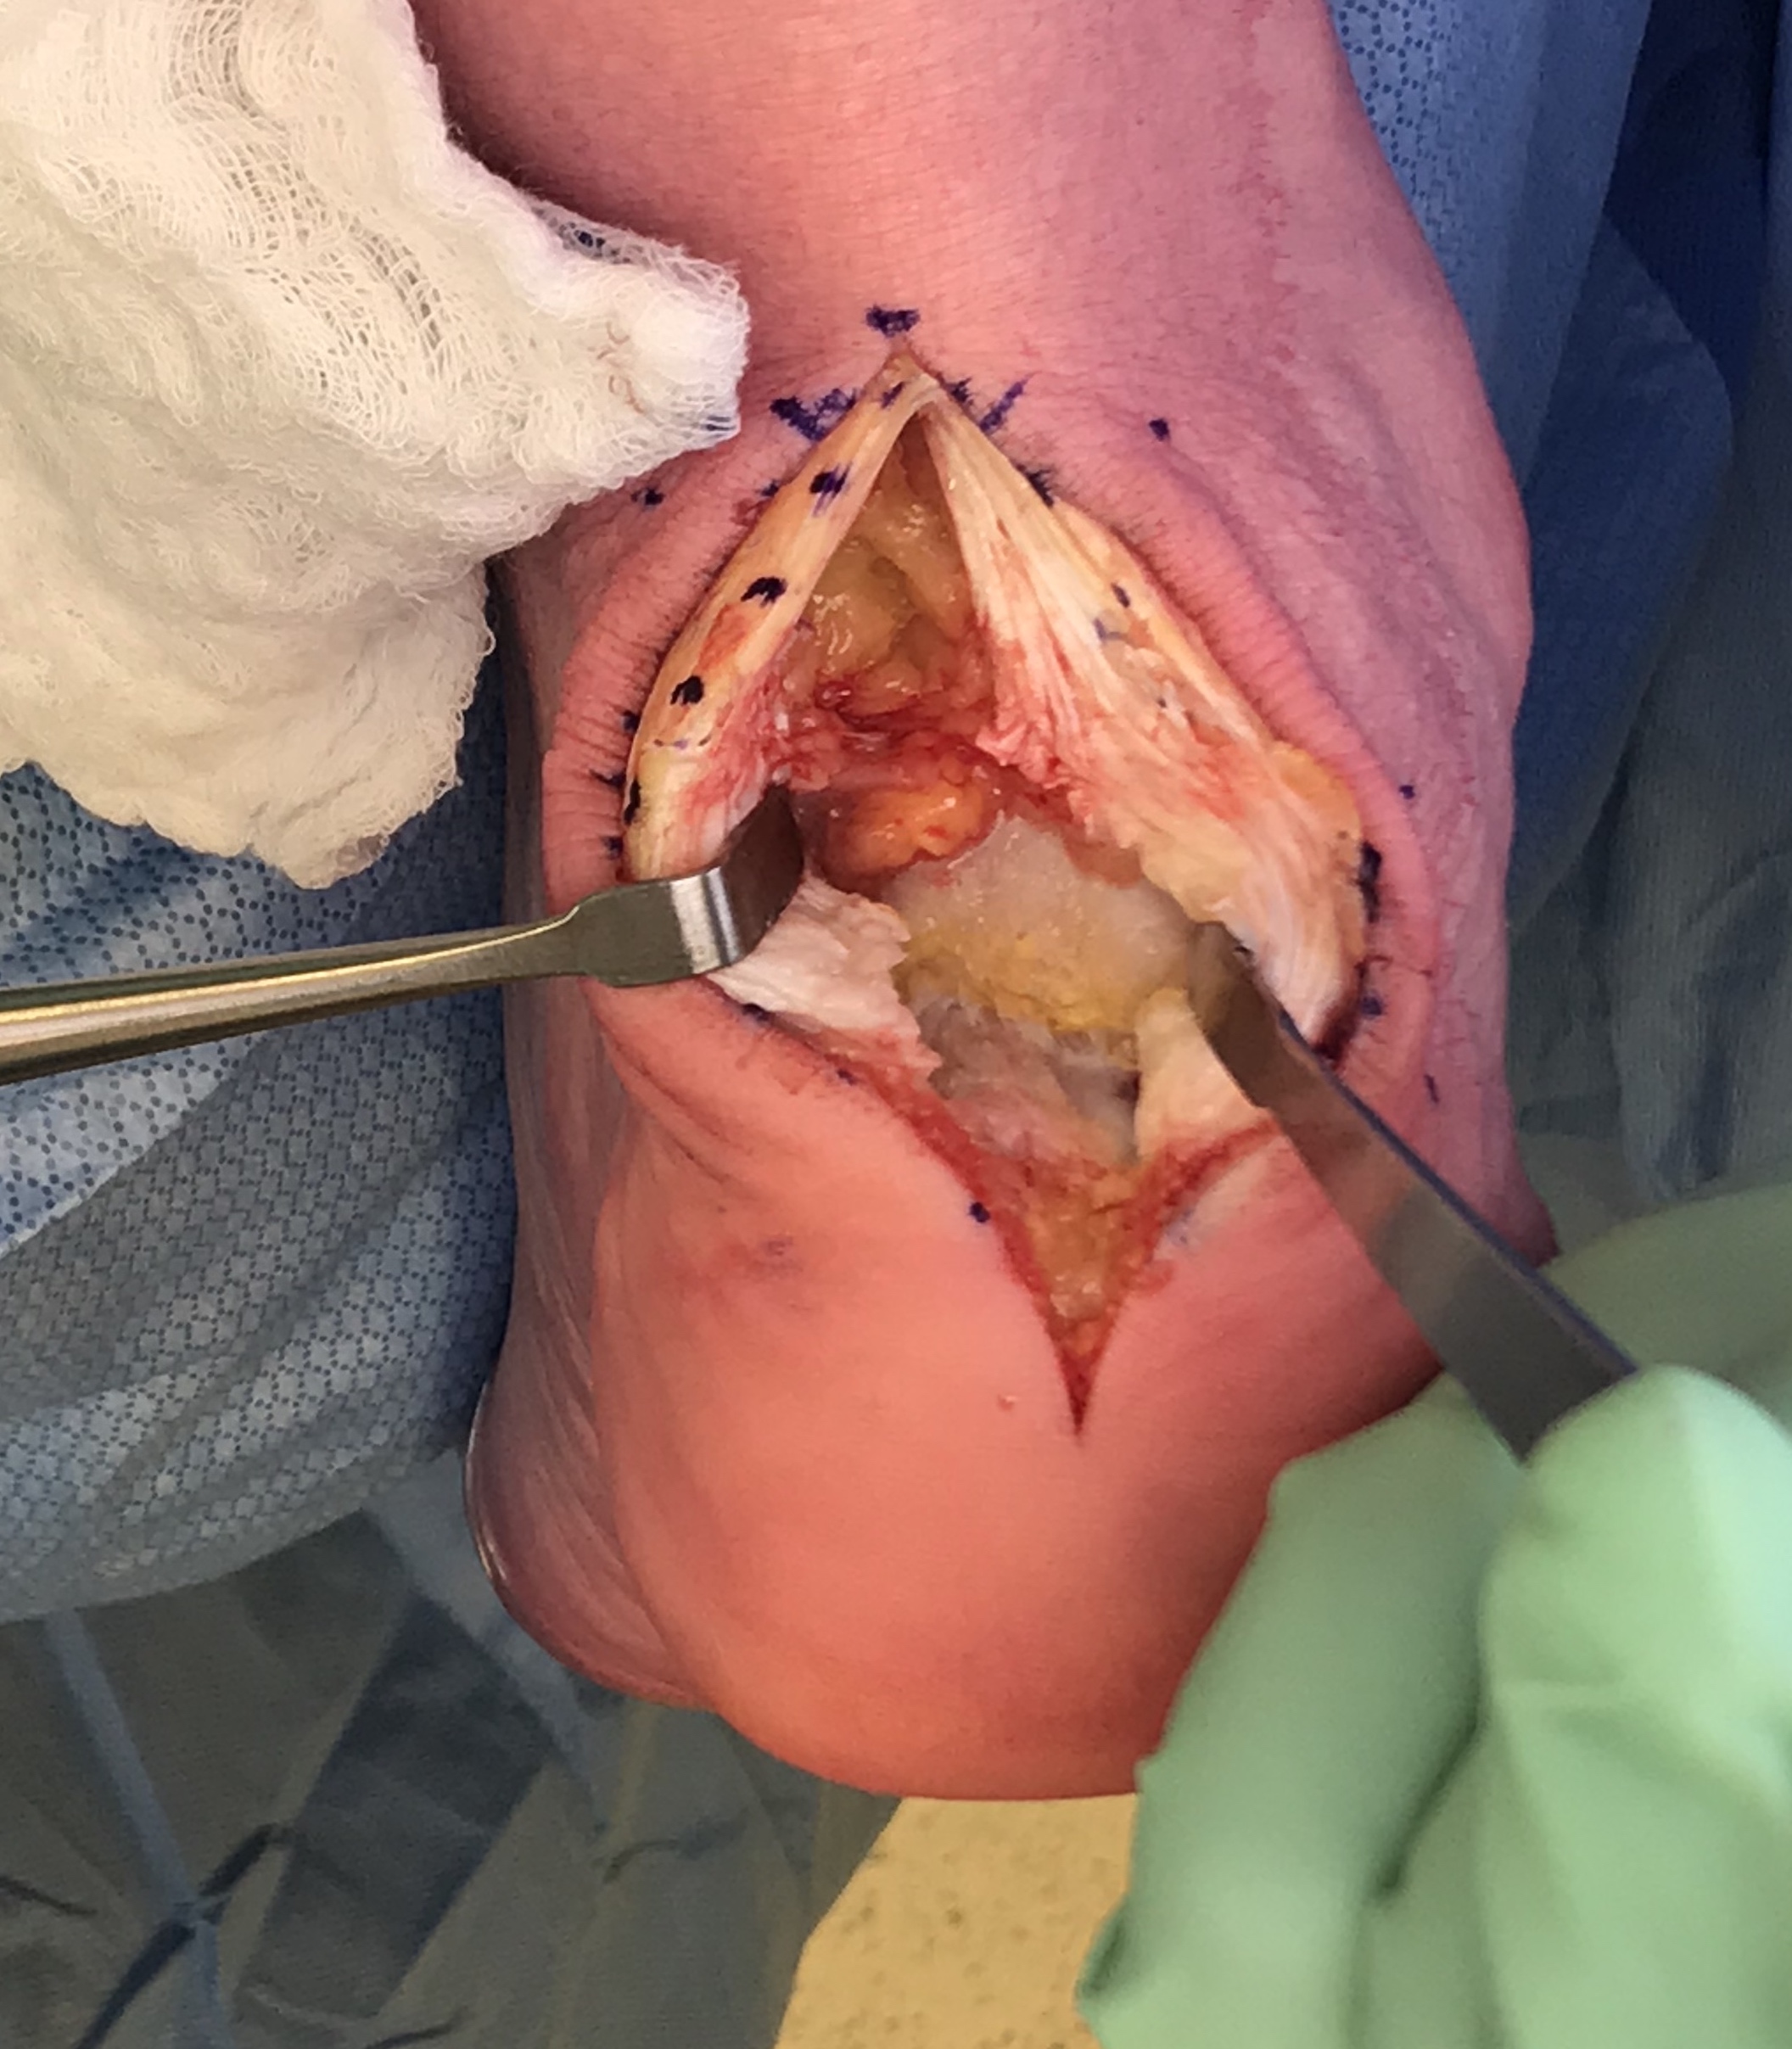

Technique

Arthrex - Achilles SpeedBridge™ System

Vudmedi surgical technique video

Patient prone

- elevate ankle to allow dorsiflexion

- identify and preserve sural nerve

- central tendon split

- resect retrocalcaneal bursa

- resect posterosuperior calcaneum / Haglunds deformity

- +/- release achilles tendon insertion

- > 50% release needs repair

- +/- augment with tendon reconstruction